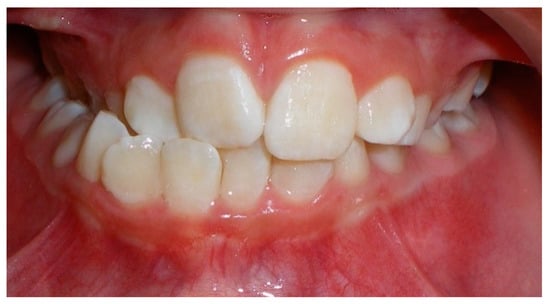

- Assessment of proposed sites of temporary anchorage device (TAD). Figure 11, Figure 12, Figure 13 and Figure 14 show correction of the Class II molar relationship using a temporary anchorage device. Figure 11 shows a pre-treatment intraoral photograph of the right side. The Class II molar relationship can be observed. Figure 12 shows coronal, sagittal and axial views, as well as a volume rendering of CBCT that was acquired in order to assess the site of the temporary anchorage device. Figure 13 shows an intraoral photograph of the right side, in which the TAD was placed mesial to the maxillary first molar, and a power chain was attached from this TAD to a hook placed distal to the lateral incisor. Figure 14 shows a post-treatment intraoral photograph showing improvement of the Class II molar relationship after removal of all orthodontic appliances.